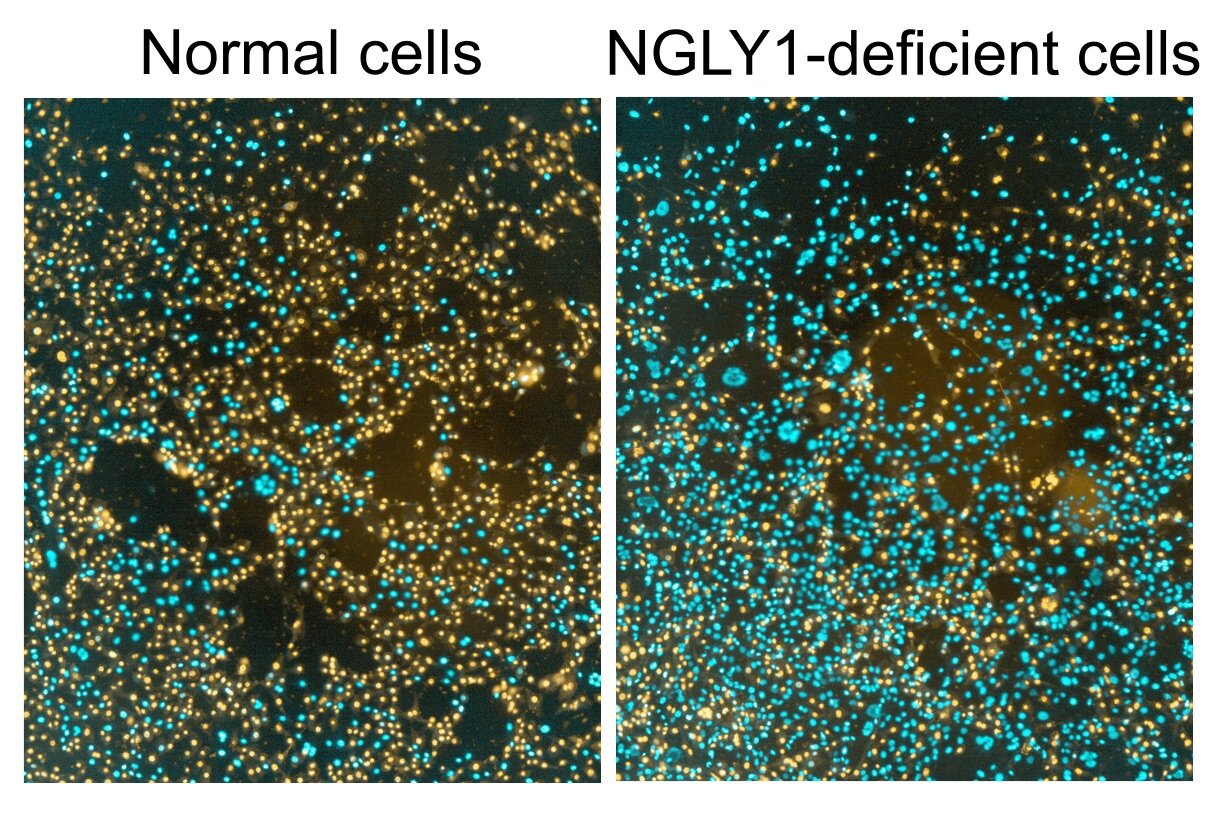

Иллюстрации из Cell Discovery: Удивительный мир науки через фотографии

Раздел: Фотоэссе